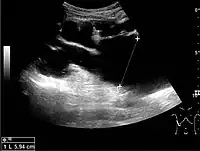

Figure 15. End-stage hydronephrosis with cortical thinning. Measurement of pelvic dilatation on the US image is illustrated by ‘+’ and a dashed line.[1]